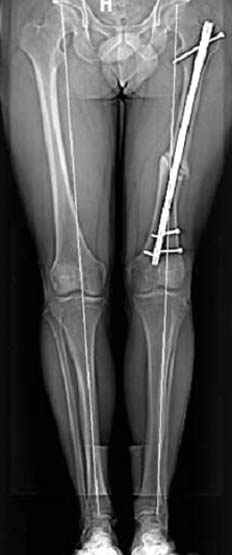

На рисунке N1 предоперационный план лечения ложного сустава шейки бедра- линия ложного сустава, угол и направление введения импланта, клиновидная остеотомия в градусах и миллиметрах, второй снимок после коррекции, расчет, на сколько удлиняется конечность и размеры импланта;

N3 рисунок окончательный снимок, после операции моя рентгенограмма должен выглядеть примерно как эта картина. На N4 снимке клин перед удалением; N5 послеоперации 3 нед.; N6 окончательная рентгенограмма.

пластическая модель; и коррекция бедра аппаратом Илизарова.